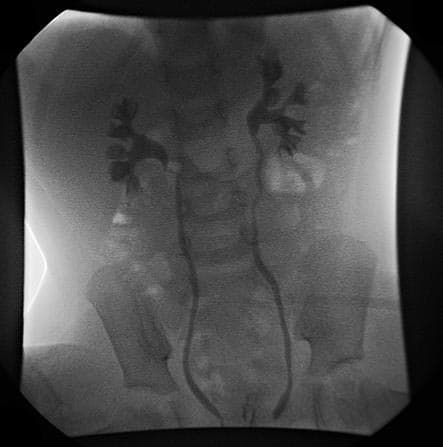

Le reflux vésico-urétéral (RVU) se définit par le passage, à contre-courant, de l’urine vésicale dans l’uretère et le rein (voies urinaires supérieures). Sa mise en évidence est essentiellement radiologique et isotopique. Le RVU traduit une incompétence du système valvulaire de la jonction urétéro-vésicale. L’uretère, à partir de son entrée dans la vessie, décrit un trajet oblique intra-mural puis sous muqueux et va déboucher à l’angle du trigone. Au niveau du hiatus urétéral, des fibres du détrusor récurrentes se détachent du versant extra-vésical et se fixent sur l’adventice urétéral amarrant ainsi l’uretère à son entrée dans la vessie. Les fibres du détrusor qui entourent l’uretère supra et intra-hiatal forment la gaine de Waldeyer. L’uretère glisse sous la muqueuse vésicale. Il repose en arrière sur le muscle détrusor. Dans son trajet sous muqueux, l’uretère est entouré de son adventice et de vaisseaux. Toutes ces fibres musculaires deviennent longitudinales. La longueur totale du trajet sous muqueux est diversement appréciée. Lorsque la vessie est vide ou partiellement remplie, la pression vésicale est de l’ordre de 10 – . Cette pression est suffisante pour comprimer la portion sous muqueuse et empêcher le reflux. L’uretère évacue l’urine par des contractions péristaltiques. Lors de ces contractions, la pression intra-urétérale est de l’ordre de 20 – . Quand la contraction arrive au niveau de l’uretère sous muqueux, elle raccourcit et élargit cette portion, mais le reflux ne peut pas se produire à cause du gradient de pression entre l’uretère et la vessie. Lorsque la vessie est remplie et que le détrusor fibrille, la pression vésicale augmente et le gradient de pression vessie – uretère s’inverse avec une pression vésicale de 35 – . La valve passive agit par un double mécanisme d’étirement de la portion intra-murale secondaire à la destruction vésicale, et de compression du segment sous muqueux sur le détrusor qui s’oppose au gradient de pression vessie () – uretère ().